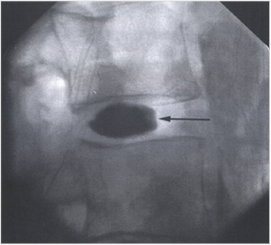

추간판 조영술

- 고주파수핵감압술

- 고주파수핵감압술은 디스크내장증, 경도의 추간판 손상 및 탈출증시 시술하는 방법으로써 고주파를 발산하는 가느다란 카테터를 실시간 방사선촬영하에 디스크 내부로 삽입하여 손상된 디스크 내부를 고주파 열로 태워서 손상된 섬유테의 통증을 일으키는 부위를 제거하여 증상을 완화하는 치료입니다.